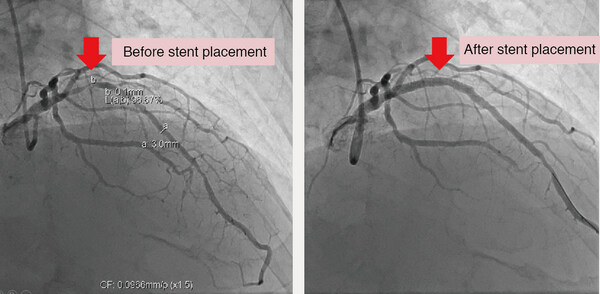

Treadmill Exercise Test AI-Assisted Interpretation System indicated that Mr. Chen had 72% risk of significant coronary artery stenosis. His coronary angiogram showed 99% stenosis in the left anterior descending branch. With percutaneous coronary intervention and stent deployment, he recovered well.

Mr. Chen, at the age of 75-year-old, experienced chest tightness and palpitation. TET showed a peak heart rate of 139 bpm and mild ST depression (depressed ST segment is a sign of inadequate blood supply in the coronary artery), and the Duke treadmill score indicated that Mr. Chen was with medium coronary artery risk (95% survival at 5 years), requiring regular monitoring but not intervention. However, to obtain a better evidence of his cardiovascular health, Dr. Hung-Pin Wu, cardiologist at CMUH, applied “Treadmill Exercise Test AI-Assisted Interpretation System” which was developed in May 2022, and it indicated that Mr. Chen’s risk of significant coronary artery stenosis was 72%. Thus, Mr. Chen underwent the coronary angiogram which showed 99%stenosis in his left anterior descending branch. Percutaneous transluminal coronary angioplasty was immediately performed and a drug-eluting stent was deployed.Luckily, Mr. Chen’s chest tightness improved, and he keeps control with diet, exercise and medications.